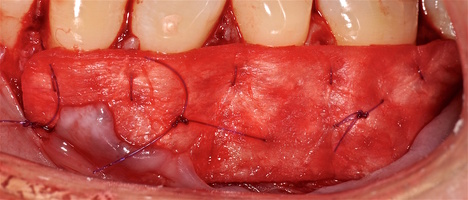

1. Генерализованные рецессии в области нижней челюсти оперировались в один этап все 12 зубов, фронтальный участок с аутотрансплантатом от 3.2 до 4.2 зубов. А дистальные участки от 3.6 до 3.3 и от 4.6 до 4.3 зубов с использованием пластического материала ТМО (dura mater) (рис. 4а-з).

Участки 3.3-3.6 зубов и 4.3-4.6 зубов были проопери- рованы зеркально по методу коронально-ротированно- го лоскута по M. De Sanctis и G. Zucchelli (2000) с одним послабляющим вертикальным разрезом в области 3.3 зуба или 4.3 зуба.

4. Фиксация пластического материала ТМО (dura mater) к поверхности корней зубов в области зоны создания необходимого объема прикрепленной десны.

5. Закрытие пластического материала слизисто-надкостничным лоскутом со смещением в корональном направлении, и фиксация слизисто-надкостничного лоскута швами; дополнительная фиксация зоны перемещенных и в будущем созданных мягких тканей десны в зоне рецессии десны для стабилизации результата операции.

Деэпителизация анатомических сосочков, обработка поверхностей корней зубов, фиксация свободного десневого аутотрансплантата и пластического материала ТМО (dura mater) швами, с полным перекрытием слизисто-надкостничным лоскутом, фиксация швами слизисто-надкостничного лоскута узловыми одиночными швами в области установки аутотрансплантата и ТМО (dura mater), двойными обвивными для слизисто-надкостничного лоскута, и крестообразными прижимающими горизонтальными швами для фиксации слизисто-надкостничного лоскута в новом положении. Обработка поверхностей корней зубов проводилась аналогично.